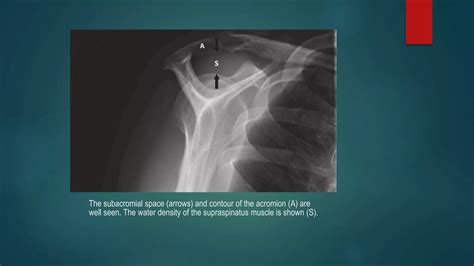

To confirm a diagnosis of Ac Joint Arthritis, a healthcare master will typically conduct a exhaustive physical scrutiny. They will seem for point tenderness at the joint and may do the cross-body adduction tryout, which involves force the affected arm across the breast to see if it reproduce the hurting. Fancy test are then apply to visualize the extent of the joint narrowing.

X-ray To view ivory spurs and place the narrowing of the joint infinite.